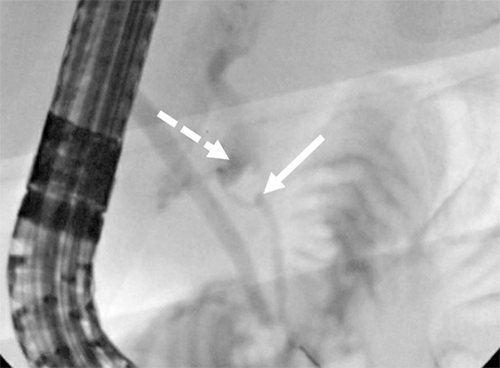

Figure 2. ERCP Fluoroscopy. Published With Permission

Endoscopic retrograde cholangiopancreatography of patient's pancreatic transection (solid arrow). Active extravasation can be seen coming from proximal duct extending into abdominal space around pancreas (dashed arrow).